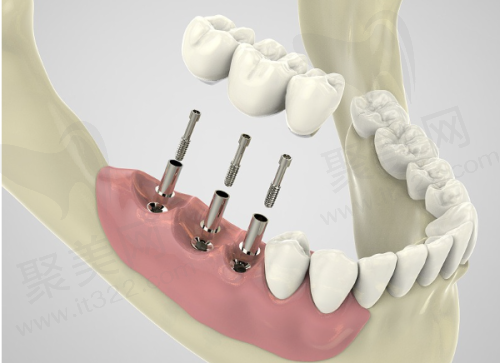

(三)手术方式对门牙种植费用的影响

手术方式不同,门牙种植费用也不同。

普通种植:就是拔牙后等伤口愈合再进行种植,这种方式费用相对较低,大概在 5000 - 15000 元。

即刻种植:拔牙后马上进行种植手术,修复快,但费用较高,大约 10000 - 25000 元。